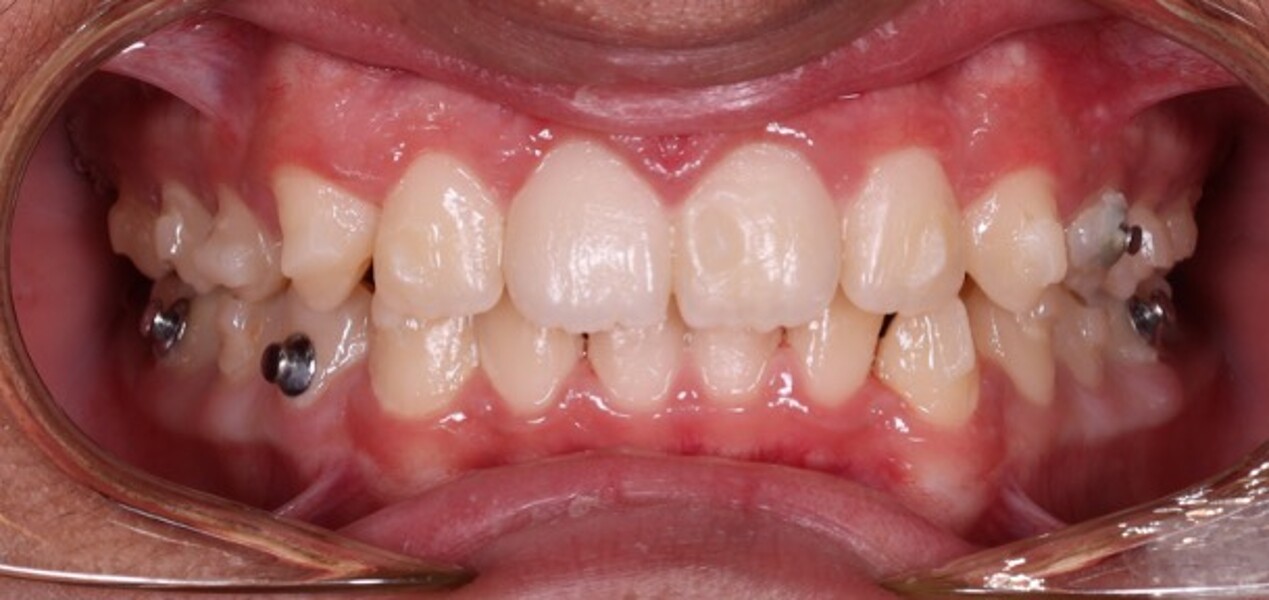

Figs. 6a–e: Intra-oral photographs after the first phase of treatment.

At the end of the first phase of treatment, the clinical findings included (Figs. 5 & 6):

Class I molar and canine relationships on the left side;

half-cusp Class II relationships on the right side;

normal overjet (2.0 mm) and overbite (2.5 mm); and

a posterior open bite, particularly on the left side.

Cephalometric analysis showed that the sagittal discrepancy had been significantly reduced (ANB = 3.7°; Wits = 1.8 mm). Mandibular length remained below normative values.